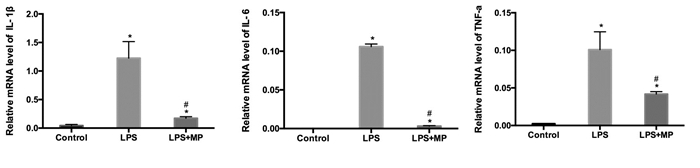

LPS处理小鼠48 h,其肝组织内TNF-α、IL-6、IL-1β mRNA相对表达量(10.09±4.73,1.06±0.68, 1.22±0.50)显著高于正常对照小鼠(0.24±0.05,0.01±0.01,0.04±0.03);而LPS+MP组TNF-α、IL-6、IL-1β mRNA相对表达量(4.18±0.81, 0.31±0.14, 0.17±0.05)显著低于LPS 48 h组表达量,差异有统计学意义(F=21.495,P=0.002;F=10.948,P=0.008; F=17.694, P=0.001)(图 4)。

|

| 对照组、LPS组、LPS+MP组三组间肝组织炎症因子mRNA表达变化,a表示与Control组(生理盐水组)比较P < 0.05;b表示与LPS组比较P < 0.05 图 4 小鼠肝组织TNF-α、IL-6、IL-1β mRNA表达变化(48 h) Figure 4 The mRNA levels of TNF-α, IL-6, IL-1β in livers of mice |